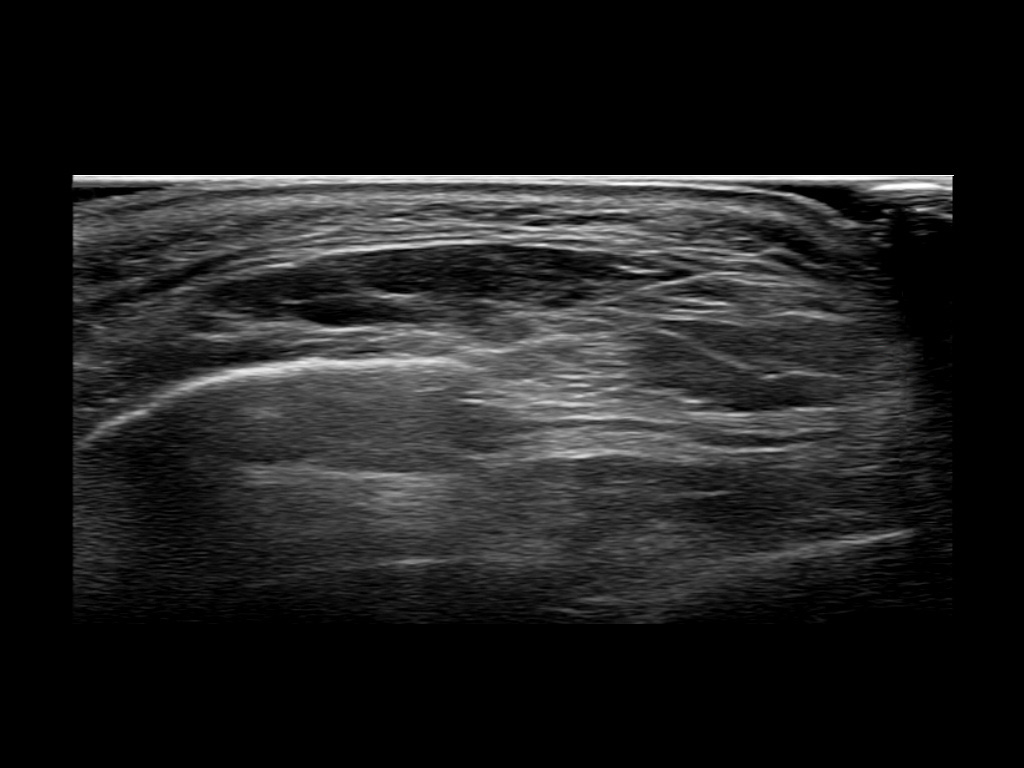

Filler behavior - Temple zygoma US

Study the first image to recognize the different layers. If you are sure about the layers, swipe to the second image to view the answer (if applicable).